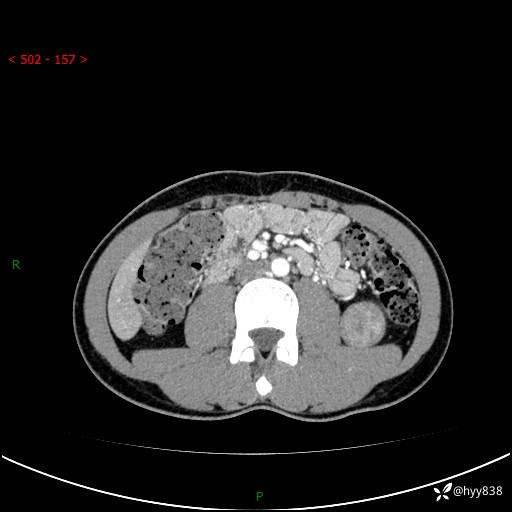

年轻男性,发现左肾占位1天。“非好病例”我不发,误诊率高---(有结果)

现病史:患者昨日中午进食后出现明显腹痛,腹泻,在我院急诊科行补液及对症治疗,双肾输尿管彩超提示左肾占位(5.2*4.3cm),平素无明显腰痛,无再发肉眼血尿等情况,现为求处理左肾占位,遂来我院,门诊以左肾占位收治入院。 患者起病以来,精神、食欲、睡眠尚可,大便可,小便如上,体力体重无明显下降。

双肾CT平扫+增强(三期)